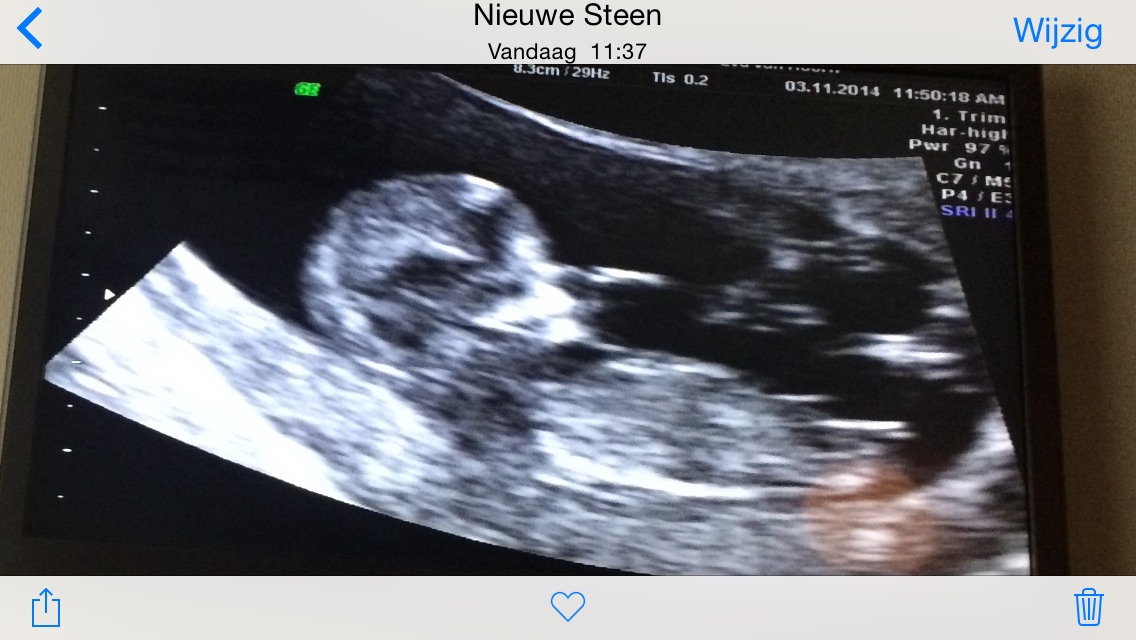

These are all the photos I have I hope the nub is visible.

Beautiful Girl nub :)

All girl there!

Girl nub for sure. Congrats.